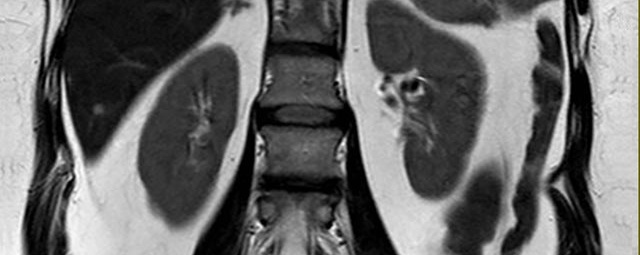

• Nieren

• Abklärung der Ursache einer Harnstauung (MR-Urographie)

• Abgrenzung gutartiger (z.B. Zysten) von bösartigen Nierenerkrankungen (Nierenzellkarzinom)

• Auffälligkeiten an Nebennieren (z.B. Adenom, Karzinom)